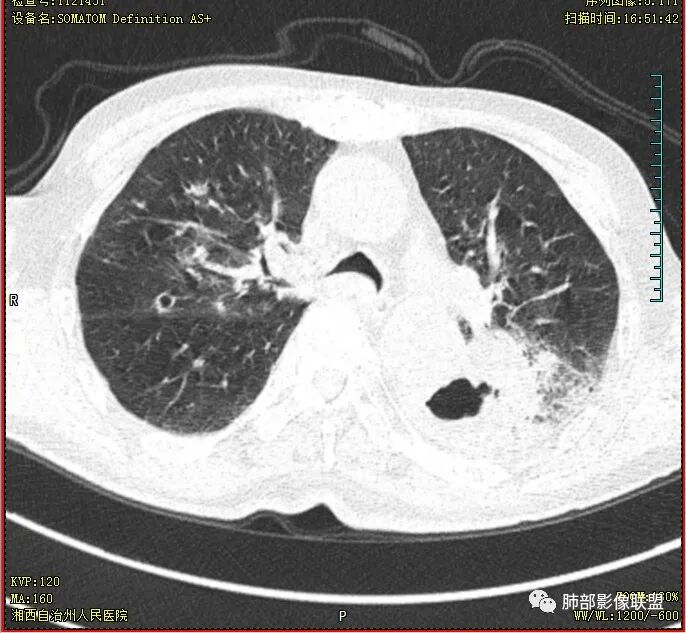

老年男性,肺气肿,左肺下叶空洞,壁厚薄不均,见液平,下叶支气管阻塞,不均匀强化,伴两肺斑片及树芽影,考虑左肺下叶癌性空洞(鳞癌)并感染及两肺结核

双肺多发结节影,树芽征,小叶中心分布,左肺下叶不规则空洞,洞内壁光滑,见液平,洞壁似与支气管相通,增强扫描明显强化,可见血管造影征。三周左右复查空洞明显缩小。

双肺结核的背景

左下肺空洞伴液平,短期变化,考虑存在感染。

老年男性,痰中带血,双肺多发点片状阴影,左肺下叶可见空洞影,有液平,不均匀强化,局部低密度区边界不清晰,复查病灶范围缩小,空洞消失,结合病史肿标增高,首选考虑肿瘤合并肺脓肿,鉴别淋巴瘤,结核。

双肺边界较清楚的斑点状影、树芽征,结合T-SPOT阳性,长病程,体重减轻等,继发性肺结核是应当考虑的,至少作为基础疾病之一。